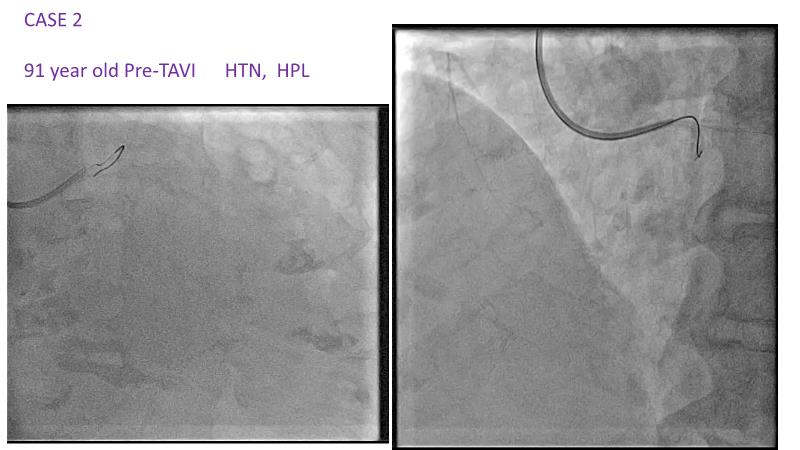

With this session, keep up to date on the evidence, trials and outcome data for intravascular lithotripsy in severely calcified lesions. Learn how to use this technique in real-world patients and understand its role in the treatment algorithm for severely calcified coronary lesions.

- To know the evidence, trials and outcome data for intravascular lithotripsy in severely calcified lesions

- To learn how to use intravascular lithotripsy in real-world patients with severely calcified coronary lesions

- To understand the appropriate role of intravascular lithotripsy in the treatment algorithm for severely calcified lesions